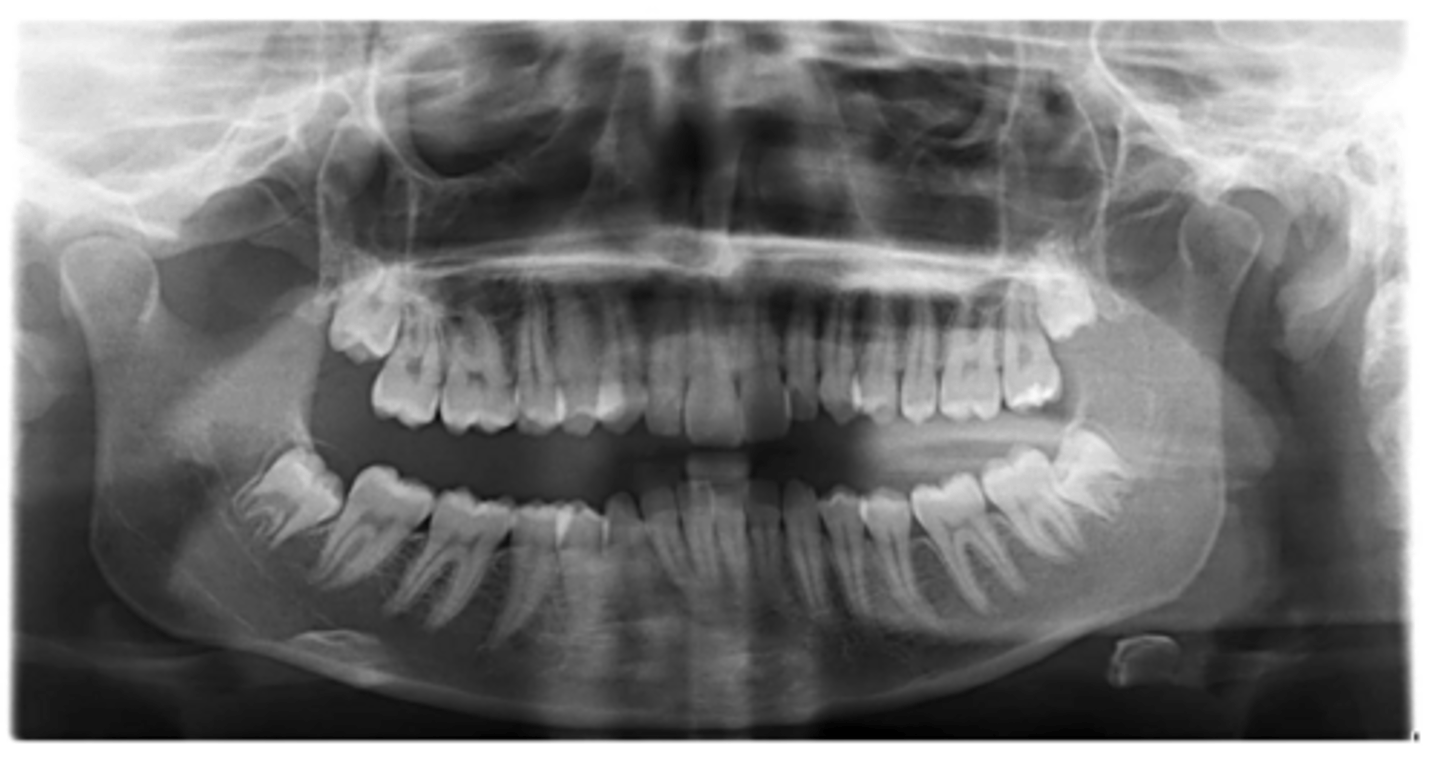

Yes - #2, also #27?

Dilacerated roots?

No

Are there congenitally missing teeth in the maxillary arch?

Are there congentially missing teeth in the mandibular arch?

Any supernumerary teeth?

Yes - mandibular second molars

Any impacted teeth?

Yes

Are the condyles symmetrical?

Maybe in the upper molars

Are there any dilacerated roots?

Are there congenitally missing teeth in the mandibular arch?

Are there any supernumerary teeth?

Are there retained primary teeth?

A little bit

Is there crowding?

Is there any pathology?

Possibly #20